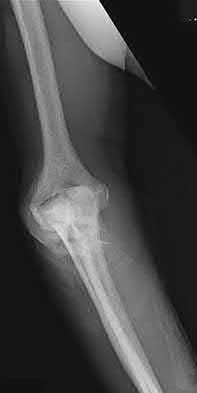

1. # A 32-year-old male sustains the injury shown in Figure A and undergoes treatment as shown in Figure B. Following placement of this implant, what is the best technique to confirm it is not too proud proximally?

1. Lateral radiograph of the knee

2. AP radiograph of the knee

3. Oblique radiographs of the knee

4. Merchant radiograph of the knee

5. Internally rotated 45 degree view of the knee Corrent answer: 1

The safe zone for tibial nail placement as seen on radiographs is just medial to the lateral tibial spine on the anteroposterior radiograph and immediately adjacent and anterior to the articular surface as visualized on the lateral radiograph.

Tornetta et al specifically located the safe zone for nail entry in a study using fresh frozen cadaver knees. The authors found that the safe zone for nail placement is located 9.1+/-5 millimeters lateral to the midline of the plateau and three millimeters lateral to the center of the tibial tubercle. The width of the safe zone averaged 22.9 millimeters and was as narrow as 12.6 millimeters.

The starting point of the of the nail can be best viewed on the lateral knee radiograph, an example of which is shown in Illustration A. Illustration B shows the "sweet spot" for nail insertion as defined by Tornetta.